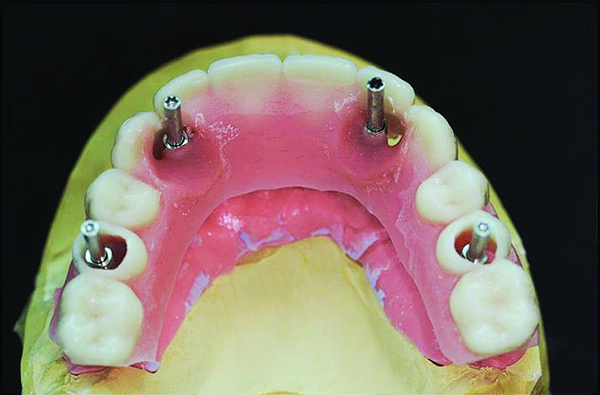

Soft tissue model—Surgical impression modi ed by adding a silicone material around the attached implant analogues before pouring the zero expansion stone for master cast fabrication.

Figure 14

Master cast with soft-tissue model fabricated from the surgical impression provides a working model for the indirect denture conversion technique.

Figure 15